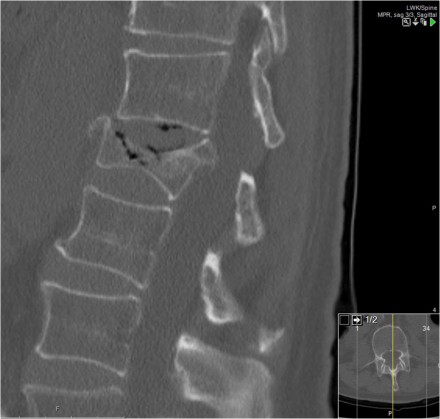

Case 6

Look at the images.

How would you describe the morphology and the PLC?

Then scroll to the next images.

The findings are:

- Morphology: Distraction - 4 points

- PLC: always torn in posterior distraction - 3 points

- TLICS based on imaging: 7 points

The key point in this case is that you should not describe this morphology as burst - 2 points.

The horizontal fractures on the posterior side and the increased

interspinous distance indicate distraction, which means a higher score

for morphology.

Always go for the highest possible score in TLICS.